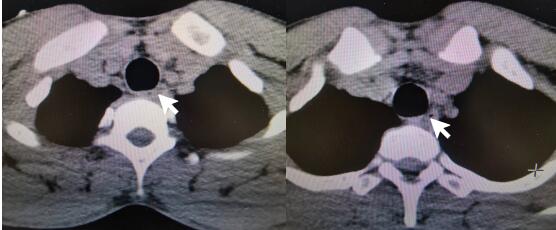

患者接触史明确,诊断为“磷酸铵盐干粉灭火剂中毒”。入院后禁食,胃肠减压,给与保护胃黏膜、抑制胃酸分泌、保护肝功能、导泻、水化碱化以及营养支持对症治疗。根据每日血清电解质结果调整补充量。约1 d后,血磷、血钾、碱剩余恢复正常范围,腹部CT:结肠内高密度影(见图 2)。心脏、双下肢静脉、腹部及泌尿系B超未见明显异常。2 d后外周血白细胞数恢复正常范围。肺部CT示右肺下叶少许炎性灶。3~4 d后血钙、肌酸激酶同工酶、超敏C反应蛋白恢复正常范围。头颅CT及MRI未见明显异常。脑电图示轻中度异常,右侧额颞部中央部略偏胜,脑地形图示右侧额颞部中央部δ频段功率相对偏高。考虑患者口咽部疼痛较前缓解,粪便隐血转阴,改为半流质饮食。5 d后,肌酸激酶恢复正常范围。食管CT:食管局部管壁稍水肿增厚,管腔狭小(见图 3)。患者住院期间未使用抗生素,转氨酶、肌酐均在正常范围,予第6天出院。本病例报道经浙江大学医学院附属第一医院伦理委员会批准,且所有临床资料均获得患者本人授权(伦理审批号:2022380)。

图 2 患者入院1 d后腹部CT平扫示结肠内高密度影